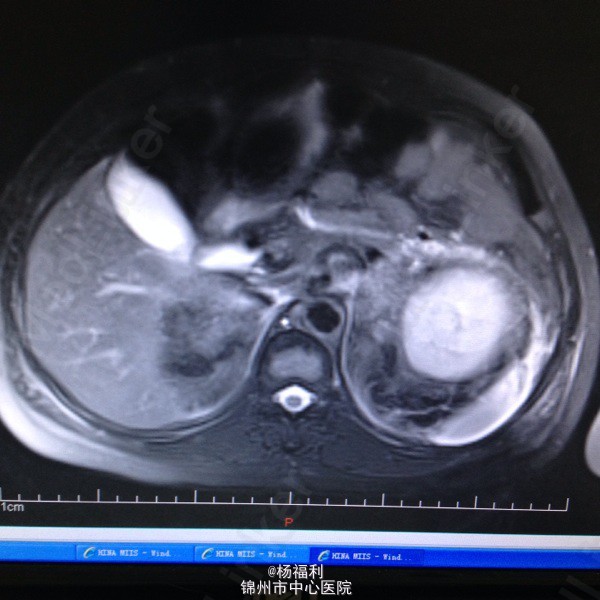

44岁女患。为消化科我会诊患者。 现病史:以上腹痛9小时为主诉入院。无发热及寒战、噁心未呕吐,无腹泻及黑便。 既往史:双眶炎性假瘤2年,口服激素治疗,并补钾。

查体:上腹部压痛,无反跳痛、右侧压痛明显,右肾区叩击痛,左肾区轻叩击痛,双输尿管走形区无压痛。 辅助检查;泌尿系彩超:双肾积水。 血白细胞:9.99*10^9。 肾功能正常。 全腹部ct及MRU检查:见图片。

诊断;真的不知道是啥病。 处理:暂时止痛处理。双肾病变。不知从哪里下手。

讨论:患者疾病和眶部肿瘤有关系吗? 和激素应用有关系吗? 最后建议患者去北京大医院进一步诊断治疗。 大神快快现身。